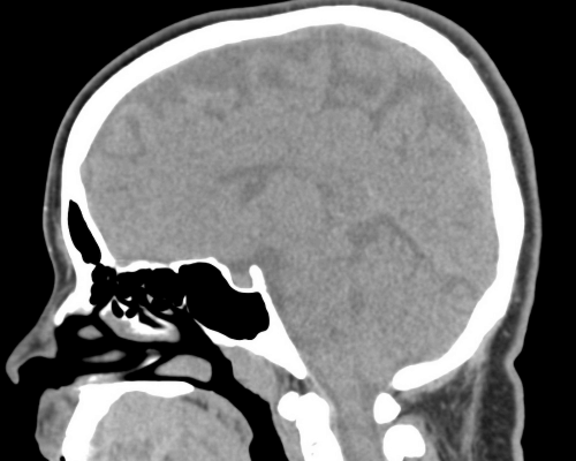

КТ головного мозга и костей черепа проводится по направлению специалиста. Во время сканирования происходит исследование структур головного мозга, вокруг мозговых структур и костей черепа.

Показания для проведения данного вида КТ: заболевания головного мозга, мозговых оболочек, костей черепа, а также травматические поражения указанных структур (переломы костей основания и свода черепа, внутримозговые кровоизлияния, оболочковые гематомы и т.д.), острое нарушение мозгового кровообращения при невозможности выполнить КТ головного мозга с перфузией или МРТ головного мозга).